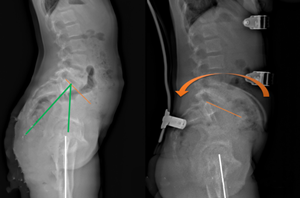

5、矢狀面靜態(tài)平衡,對矢狀面生理曲度的控制,減少平背,腰椎過度前凸的產(chǎn)生。,在全脊柱側(cè)位片上分別測量骨盆入射角(IP)、骨盆傾斜角(VP)、骶骨傾斜角(PS)、腰椎前凸角(LL)、胸椎后凸角(TK)的度數(shù),以骨盆入射角為參考下方的尺子對應(yīng)其他幾個角度的值是否在該線上,來判斷患者的矢狀面生理曲度是否處于平衡狀態(tài)。